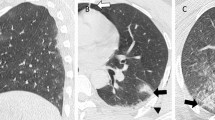

PC is primarily diagnosed using radiologic modalities. Traditionally, the diagnosis is based on plain chest radiographs (CXR), but ultrasound and computed tomography (CT) scans have demonstrated superior detection [4, 5]. Since PC develops over time, it may be missed if only a single modality is used too early or too late. The severity of PC is underestimated on initial CXR, and the full extent of PC may not become visible on CXR until 48 h after jury, lagging behind clinical signs such as hypoxia and shortness of breath [2]. CT scans have a very high sensitivity for PC, however not all PC seen on CT lead to respiratory dysfunction [4, 6]. Also, radiographic worsening of contusion on a repeated CT scan, performed at median 85 h after trauma, was not associated with a worse clinical outcome [7]. As the threshold to perform a CT scan to evaluate trauma patients is very low nowadays it can be assumed that PC, both clinically significant and insignificant, is detected more often. This creates a need to define which changes suspect for PC on CT scans will lead to worse outcomes. The aim of this systematic review was to identify the different classification systems for PC used in literature based on chest CT in the acute setting in patients who sustained blunt thoracic trauma, and to determine the association between the extent of PC measured per system and in-hospital outcomes.

As CT scans are increasingly performed on trauma patients, more PC are found than in the days that only CXR was used. Klein et al. demonstrated that PC seen only on CT and not on conventional radiographs, causes a change in clinical management in only 20–30% of cases [33]. Thus, PC not seen on CXR seems often not severe enough to affect outcomes. One of the disadvantages of only using CXR to diagnose PC is that CXR is not sensitive enough to detect early PC. CT-scans have a higher sensitivity for PC. Furthermore, an advantage of CT scans then is the fact that they can be used for volumetric analysis, and thus allow for identification of patients at increased risk of complications [33, 34].